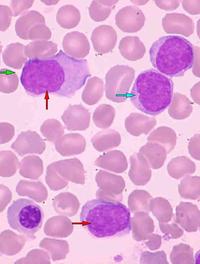

Les syndromes myélodysplasiques (SMD) constituent un groupe hétérogène d’hémopathies caractérisées par une dysplasie de la moelle osseuse [...]

Les syndromes myélodysplasiques (SMD) de faible risque correspondent aux catégories risque faible et risque intermédiaire 1 de l’IPSS [...]